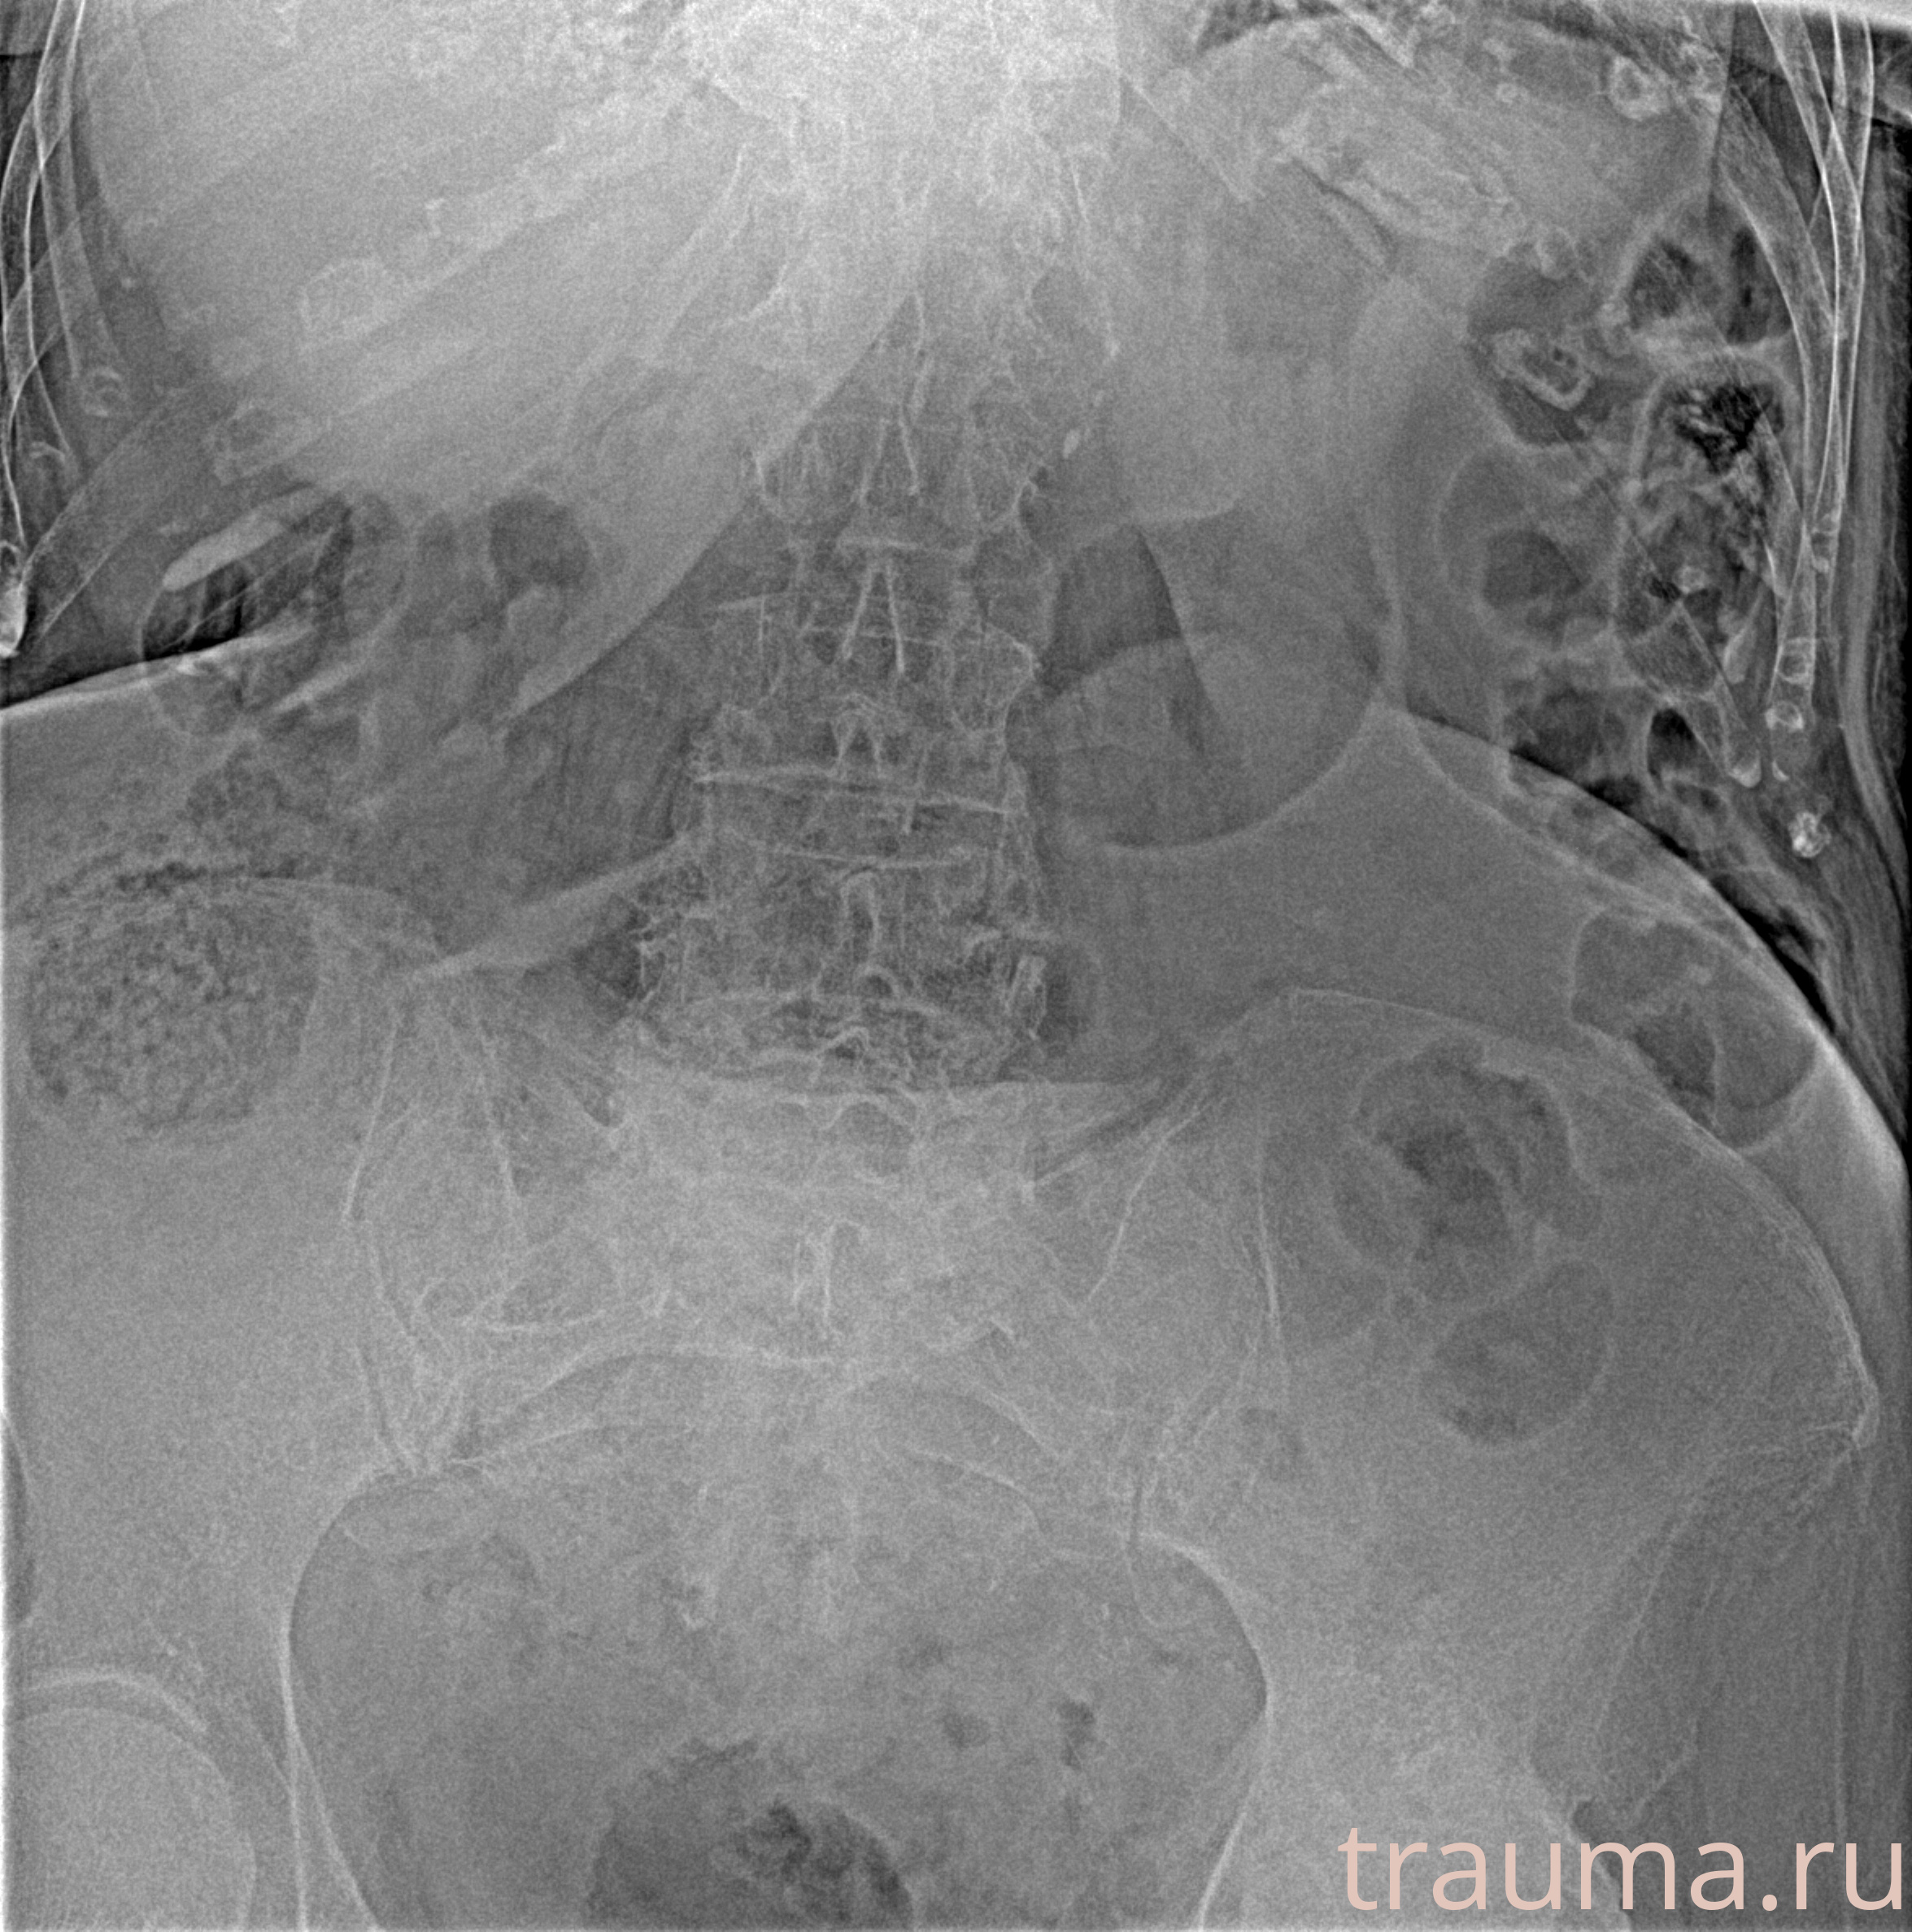

Рентген на дому: по вашему адресу приезжает врач-рентгенолог, травматолог-ортопед с мобильным рентгеновским аппаратом, проводит диагностику травмы или заболевания, делает необходимые рентгенограммы, дает рекомендации по дальнейшему лечению. Получить качественные снимки в домашних условиях возможно благодаря уникальной методике, разработанной МосРентген Центром для института  Склифосовского